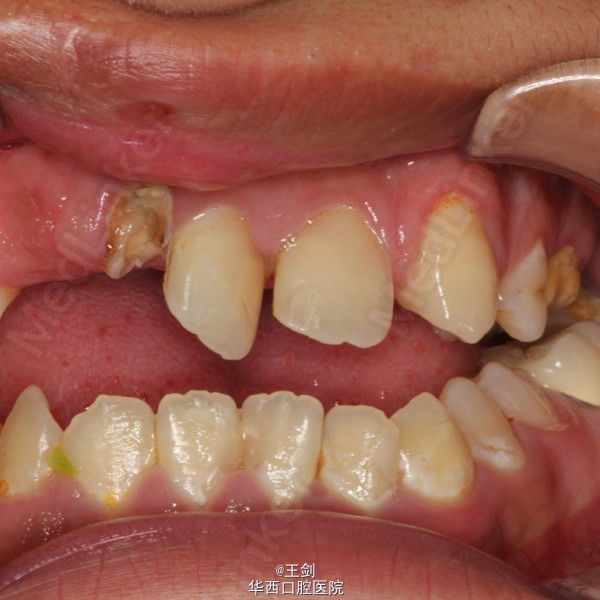

患者男,19岁,先天性唇腭裂,已行多次唇腭裂整复术,现要求进行前牙修复

12牙残根,已做根管治疗,11牙扭转,位于中线处,已做根管治疗,22牙先天缺失